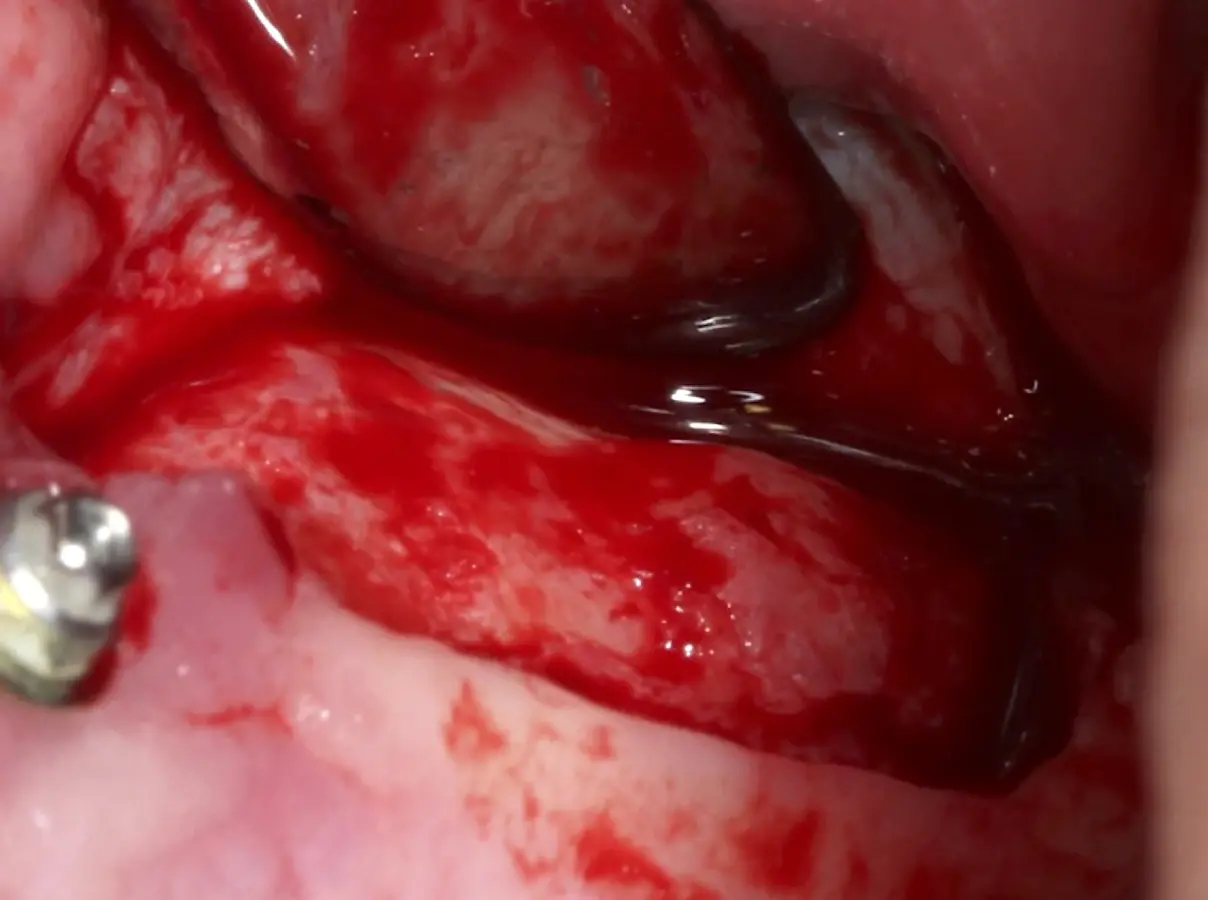

Figura 1. Incisión y levantamiento de colgajo a espesor total.

Figura 15. Incisión supracrestal y decolado a espesor total del lado izquierdo.